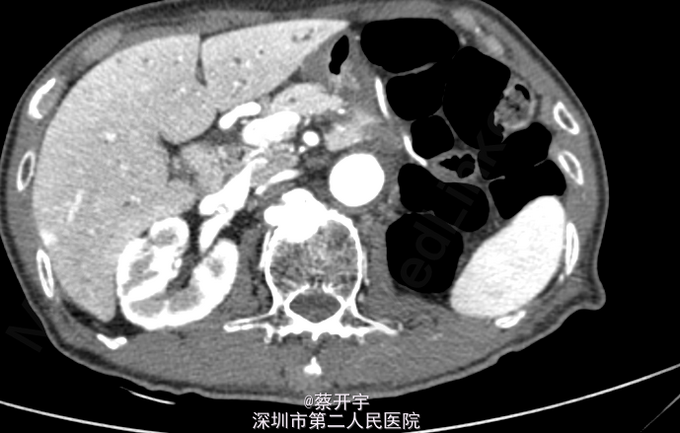

患者,男性,75岁。因“腰背痛20天”入院。 外院腹主动脉CTA示:腹主动脉中下段假性动脉瘤(最宽处57mm),累及右髂总动脉,附壁血栓形成。

查体,心肺查体未见异常。左下腹可触及一搏动性包块,与心率一致,呼吸无相关。 入院完善主动脉全程CTA检查,具体见下图。

诊断:腹主动脉瘤(肾下型) 处理:排除手术禁忌症后行腹主动脉腔内隔绝术。